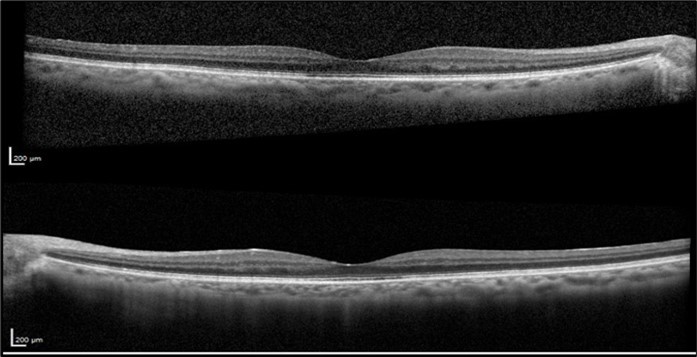

A 75-year-old female with underlying dyslipidemia and rheumatoid arthritis presented to the emergency department with a history of CME and reduced VA in both eyes (OU) for several months. She had undergone cataract surgery 20 years earlier in a different hospital and was currently using topical nepafenac, dorzolamide, and dexamethasone prescribed abroad. Initial VA in the right eye (OD) was 20/50 and in the left eye (OS) was 20/40. Fundus examination was notable for macular edema in OU. OCT OU revealed subretinal foveal fluid and intraretinal cysts (Figure 1).

Figure 1.Optical coherence tomography of both eyes revealing subretinal foveal fluid and intraretinal cysts at the patient's initial presentation to our clinic.

Optical coherence tomography of both eyes revealing subretinal foveal fluid and intraretinal cysts at the patient's initial presentation to our clinic.